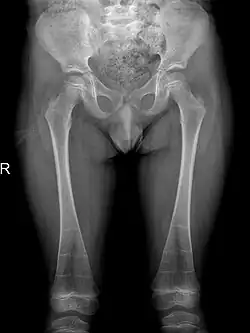

The occurrence of DSS also leads to deformities of the limbs. 80% of patients reported with abnormalities of the metaphysis such as metaphyseal flaring, radiolucent metaphyses, abnormal metaphyseal trabeculation, which is abnormal trabecula patterns in the metaphyseal region, and epimetaphyseal sclerosis. Other limbic abnormalities include progressive bowing of long bones, which is present in rare cases.[6][7]

Sclerosis of epiphyses, diaphyses, and metaphyses with increased radiolucency are key characteristics of the disease.[18] In addition, mottled metaphyseal sclerosis and widening are also present in patients.[4][9] Development of irregular patchy sclerosis along the bone can also be identified,[9] as well as metaphyseal flaring evolve towards Erlenmeyer flask deformity with nonuniform patches of sclerosis, which are especially prevalent in older patients.[10]

The metadiaphyses, a portmanteau of the metaphysis and diaphysis,[20] are bulbous and expanded with bowing and relative radiolucency. The expanded regions are also sclerotic and gives the characteristic bone-in-bone appearance.[4]